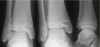

X-ray : 양과 골절(Bimalleolar fracture)